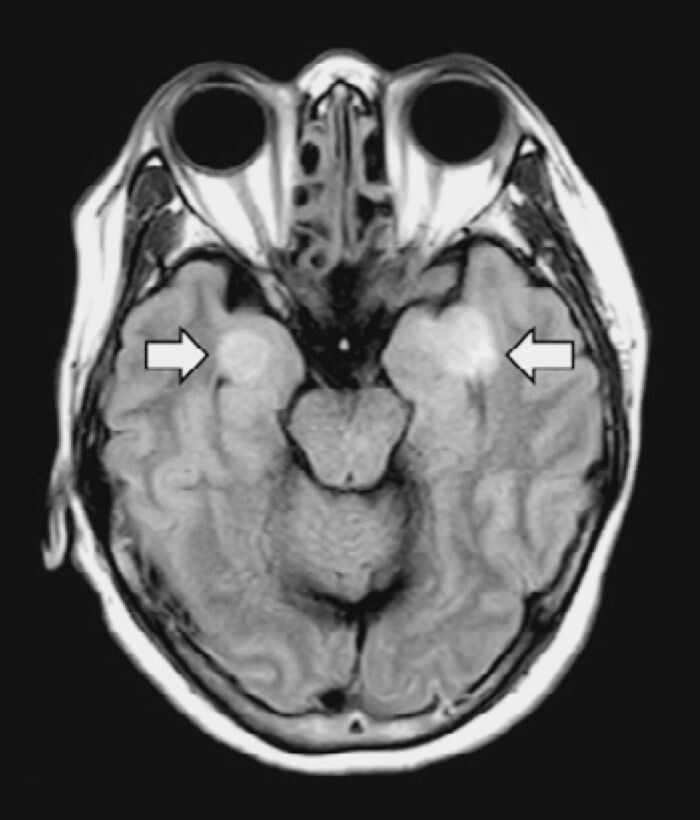

5. Мозг. У пациентов с COVID-19 наблюдаются инсульты, судороги, спутанность сознания и воспаление мозга. Врачи пытаются понять, что именно из этого вызвано вирусом.

У 58-летней женщины с COVID-19 развился энцефалит, что привело к повреждению тканей головного мозга (стрелки). Н. ПОЯДЖИ  И СОАВТ. ,  РАДИОЛОГИИ , (2020)